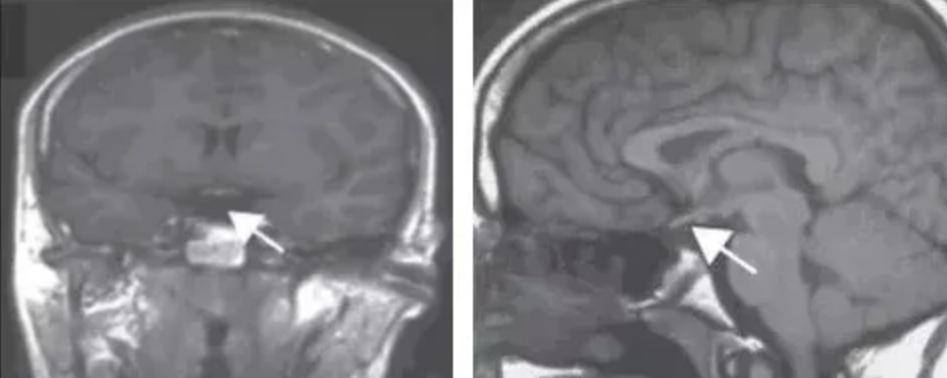

內分泌科進一步檢測了李明的垂體相關激素水平。結果顯示,其多項激素水平明顯低於參考值下限。影像檢查也顯示,患者的垂體柄纖細,腺垂體發育不良,垂體後葉異位。

醫師提醒,垂體柄阻斷綜合症屬於罕見病,男性和女性均可發病,可能隨著年齡增長出現不同的臨床表現,需要做磁共振檢查才能確診。近年來報導該病的文獻增加,但仍有相當多的患者未能及早診治,導致成年後面臨嚴重的健康和生育問題。對於自幼有生長發育異常的孩子,應及時到大醫院兒科和內分泌科就診,儘早補充各種激素、促進生長發育,真正做到早發現、早治療。